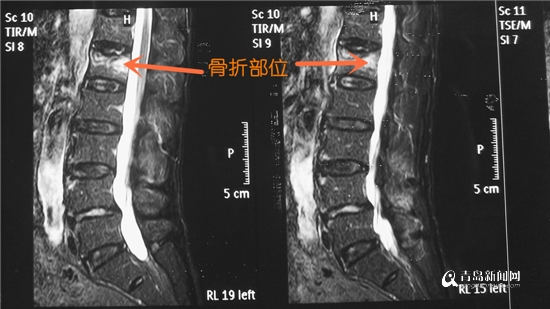

據(jù)悉,摔倒后矯大爺腰部疼痛以致不能活動,市胸科醫(yī)院外科主任趙明偉綜合老人的查體表現(xiàn)和影像資料,確診為“腰1椎體骨折”。為了能讓老人盡早下床,減少老年患者長期臥床的并發(fā)癥,趙明偉建議采取椎體成形術(shù)的微創(chuàng)治療方法。